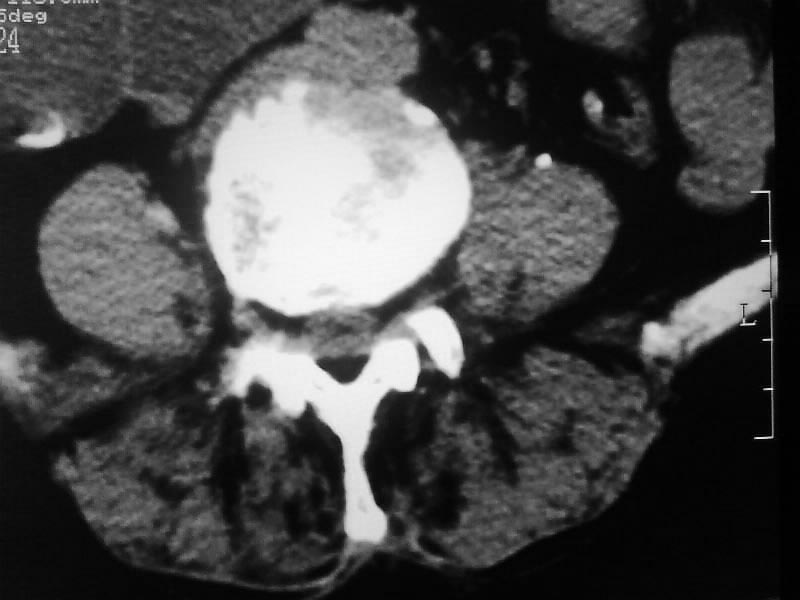

定位相示l2呈楔形改变(ct示陈旧性骨折改变,图像未传),l4.5椎体融合,以下是l4.5ct平扫.请各位看看,

考虑结核(有破坏、硬化及死骨)。

1、三四椎体结核,2、水平骶椎。

1、l1压缩性骨折(陈旧性)。

2、l3、4椎体结核。

就是腰1压缩性骨折,腰3\\4椎体结核(融合),水平骶椎.

支持 l1椎体陈旧性压缩性骨折;l3、4椎体结核(融合);水平骶椎。